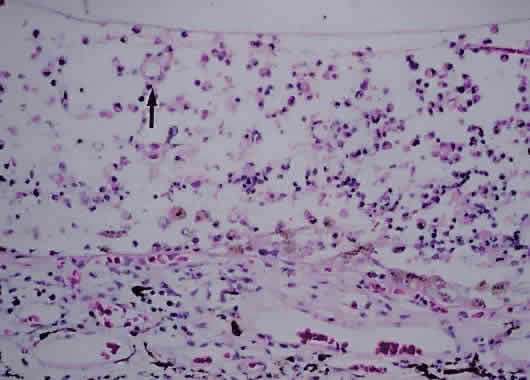

Much attention has been given to the histopathologic nature of the “snowbanks,” which has been studied by both light and electron microscopy.52,54,56–58 These fibrovascular-glial proliferations are found over the inferior pars plana and peripheral retina. They are composed of dense connective tissue derived from condensed, collapsed vitreous and often are vascularized. These vessels may reveal features of high endothelial venules (Fig. 8). Such endothelia are known to play a role in the homing of activated lymphocytes.54 The cellular elements of these membranes include fibroglial cells that are believed, based on their electron microscopic characteristics, to represent fibrous astrocytes, as well as nonpigmented ciliary epithelial cells, fibroblasts, and lymphocytes (Fig. 9).52–55,59,60 The vitreous is infiltrated by chronic inflammatory cells, and despite the nongranulomatous nature of the inflammatory component in the snowbanks, vitreous snowballs have been reported to consist of epithelioid cell granulomas.52

Fig. 9. A. Photomicrograph of “snowbank” in patient with pars planitis showing a fibroglial mass with proliferated epithelial elements (hematoxylin and eosin; × 31). B. Higher magnification showing epithelial elements and glial proliferation (hematoxylin and eosin; × 80). C. Chronic inflammatory cell infiltrate in pars planitis (hematoxylin and eosin; × 200).